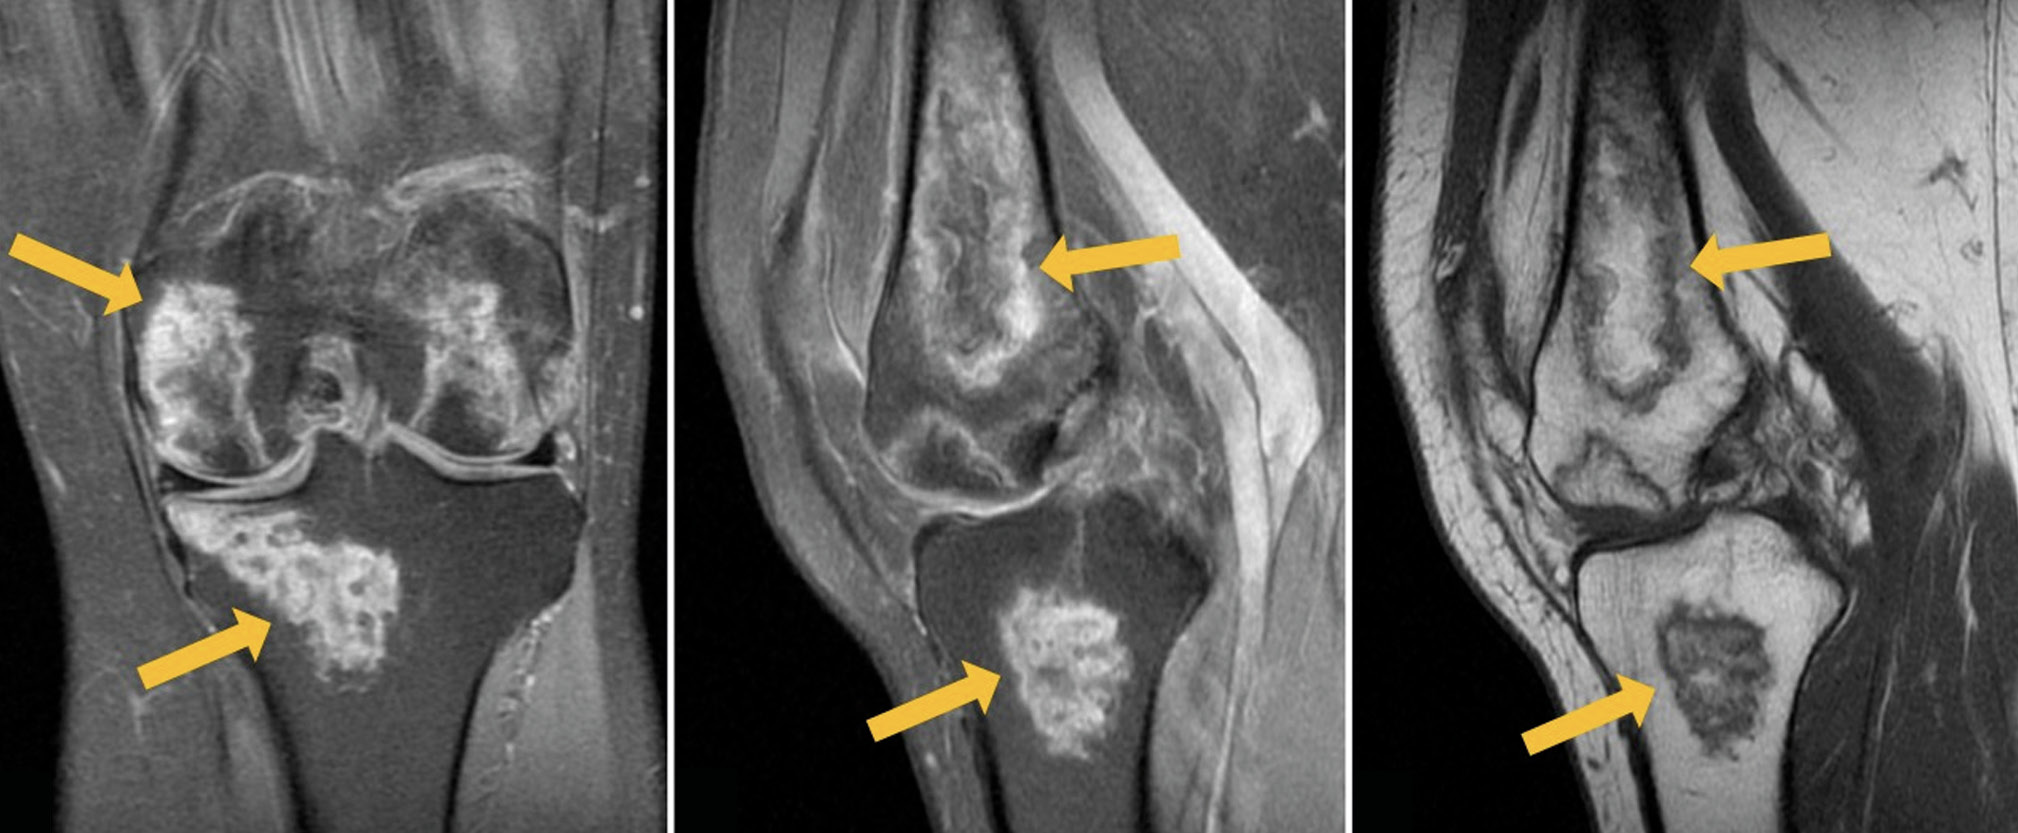

A follow-up MRI of both knee joints revealed positive changes: Previously identified lesions had become substantially less severe (Figs. 3 and 4).

Fig. 4. Follow-up MRI of the right knee joint: PDWI with fat suppression in the coronal (а) and sagittal (b) plane and T1WI in the sagittal plane (с). Thick arrows indicate areas of bone marrow edema in the form of a heterogeneous, irregularly shaped (“geographic”) MRI signal of femoral condyles and patella; thin arrows indicate the “double line” sign in the form of internal hyperintense (granulation tissue) and external hypointense (osteosclerosis) lines on PDWI.